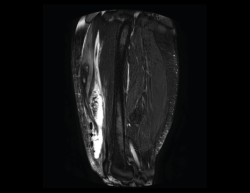

4.2. Infartos

Los infartos medulares óseos aparecen en el 0,06% de los pacientes a quienes se les ha realizado una RM del aparato locomotor. Se presentan como lesiones segmentarias, puramente medulares, sin afección cortical, normalmente múltiples y que afectan predominantemente a los huesos largos de las extremidades, sobre todo las inferiores. La RM es esencial en el diagnóstico por imagen, apareciendo como lesiones óseas intramedulares de contornos serpiginosos hipo- o isointensos en secuencias T1 e hiperintensos en T2. Por tanto, la RM es el instrumento crucial en las fases iniciales, ya que permite caracterizar las lesiones y proceder a su diagnóstico temprano(19)(Figura 52).

Figura 52. A: corte de secuencia coronal T2 Fat-Sat con infartos óseos en el fémur y la tibia; B: corte de secuencia sagital T1 con infartos óseos en el fémur y la tibia.